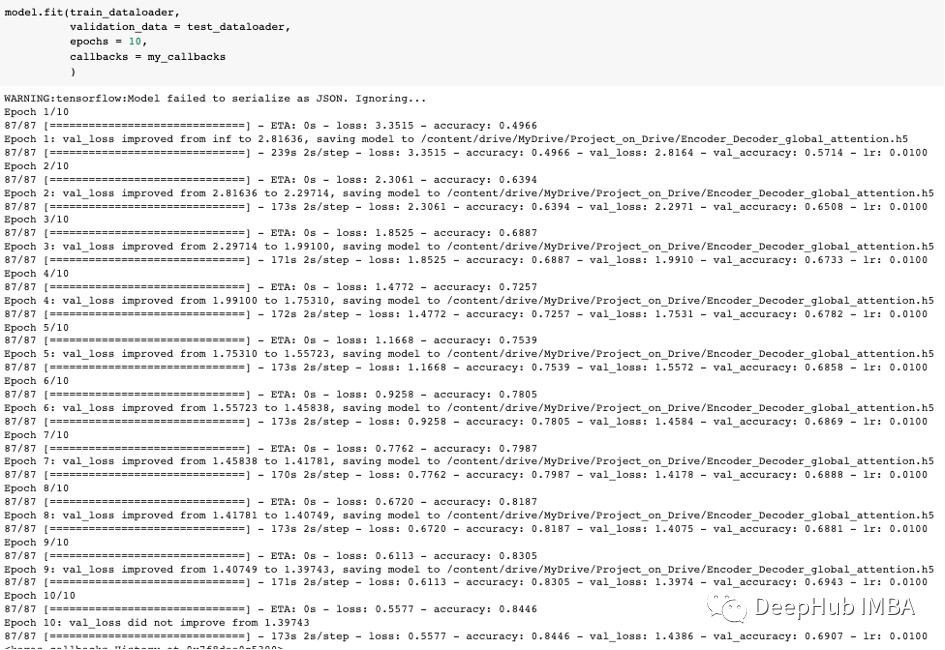

模型训练了10轮,可以看到损失为0.5577,精度为0.8466,验证损失和精度分别为1.4386和0.6907,如果我们继续运行模型,可以得到更好的损失和精度,但看起来模型是过拟合的,因为得到了10轮的最佳结果。

可视化可以看到,评估精度随着迭代次数的增加而增加,评估损失随着迭代次数的增加而减少,这是一个很好的迹象,表明权重正在收敛,所有导数都在良好的范围内,没有爆炸或消失的梯度。